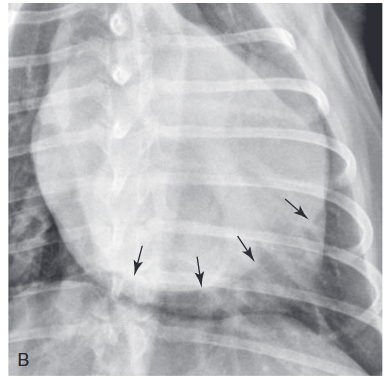

This double wall appearance is often due to enlargement of which cardiac chamber?

a) right atrium

b) right ventricle

c) left atrium

d) left ventricle

A